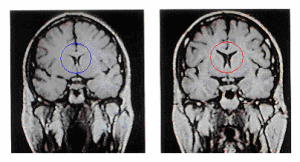

海馬神經幹細胞激活療法遼寧省精神衛生防治基地的海馬神經幹細胞激活療法深層剖析過心理障礙、精神障礙類疾病發作的根源,同時從病理病因入手,實現由點到面、由腦部到整體的突破性總結,利用其自身在1認知學、2精神學、3神經學、4康復醫學、5內分泌學、6免疫學等多學科領域所取得的成功性的科學研究和臨床經驗,為精神疾病的進一步探索奠定了非常有價值的治療新思路,開創了東方腦部檢測的新時代,並隨之帶來精神科疾病治療的全新的面貌。